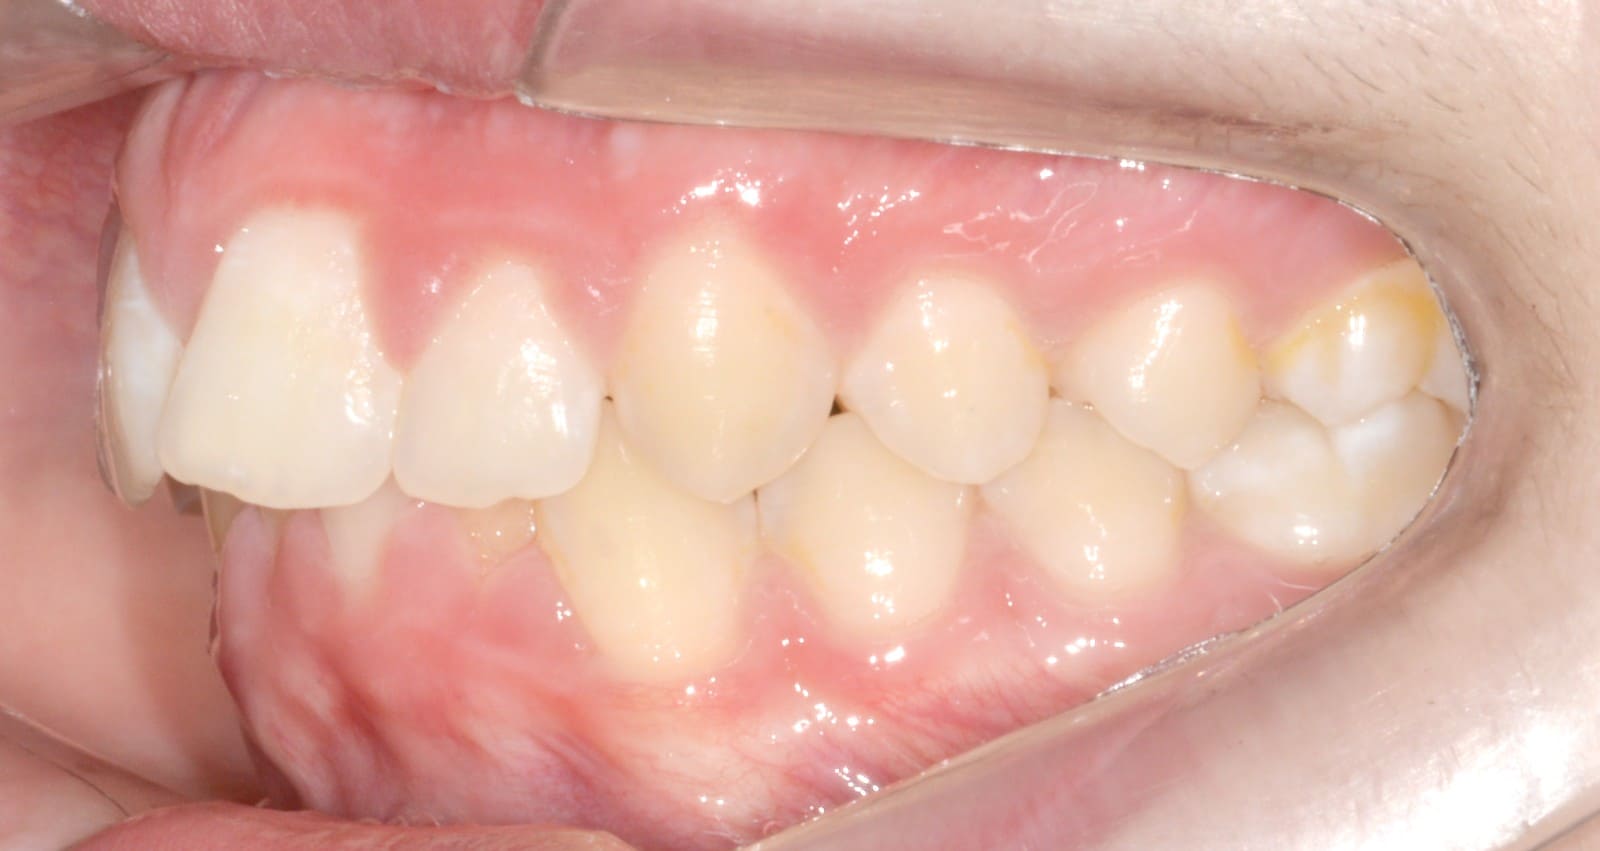

Final

- Class I relationship achieved

- Functional canine guidance on both sides

- Normal overjet and overbite achieved

- Significant improvement of overbite

- Significant improvement of overjet

- Proper axial inclination of incisors

- Curve of Spee leveled

- Arches aligned and coordinated

- Arch form improved

- Aesthetic smile line was achieved

- All treatment goals were achieved case

- Harmonic arches were achieved